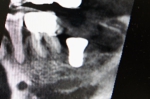

下親知らず

右下親知らずが前の歯を悪くしてしまっているので抜歯した症例。下の歯にしては珍しく3本根がある(根の数は多い方が大変)。

神経(黒い丸になっている個所)にかなり近いところに生えていて、力のかけ方を間違えると麻痺を起してしまう危険が高い。

右側の根の近くには動脈が走っておりそこへ突き抜けても大変危険。

一般的には間違いなく大学病院に送るであろう症例。